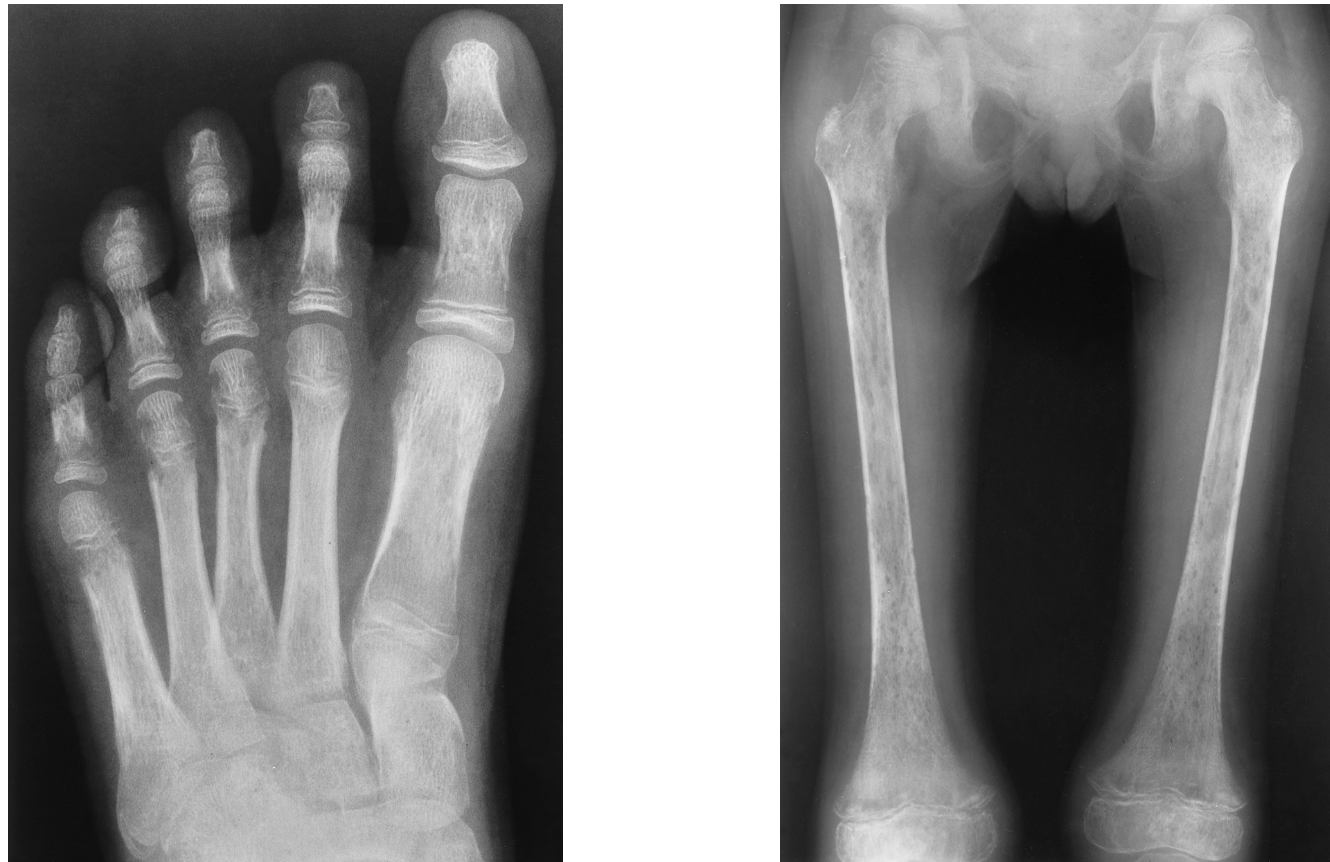

Spherocytosis

the erythrocytes have a circular rather than a biconcave shape,

making them fragile and susceptible to rupture

sickle cell anemia

is generally confined to African Americans, the hemoglobin molecule is abnormal and the red blood cells are crescentic or sickle shaped and tend to rupture.

thalassemia

A defect in hemoglobin formation which occurs predominantly in persons living near the Mediterranean Sea, especially those of Italian, Greek, or Sicilian descent

bone thinning

“Hair-on-end appearance” of thalassemia

fish vertebrae

sickle cell anemia appearance